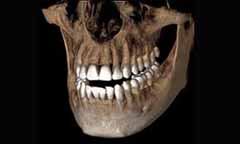

Dental cone beam computed tomography (CT) คือ เทคนิกพิเศษ ที่ใช้เพื่อการถ่ายภาพ กระดูก และ อวัยวะแข็งในช่องปากชนิด 3 มิติ ช่วยในการวินิจฉัยความผิดปกติของกระดูก บริเณศรีษะ และใบหน้า ซึ่งภาพที่ได้จะมีรายละเอียดมากกว่าการถ่ายภาพรังสีแบบปกติ